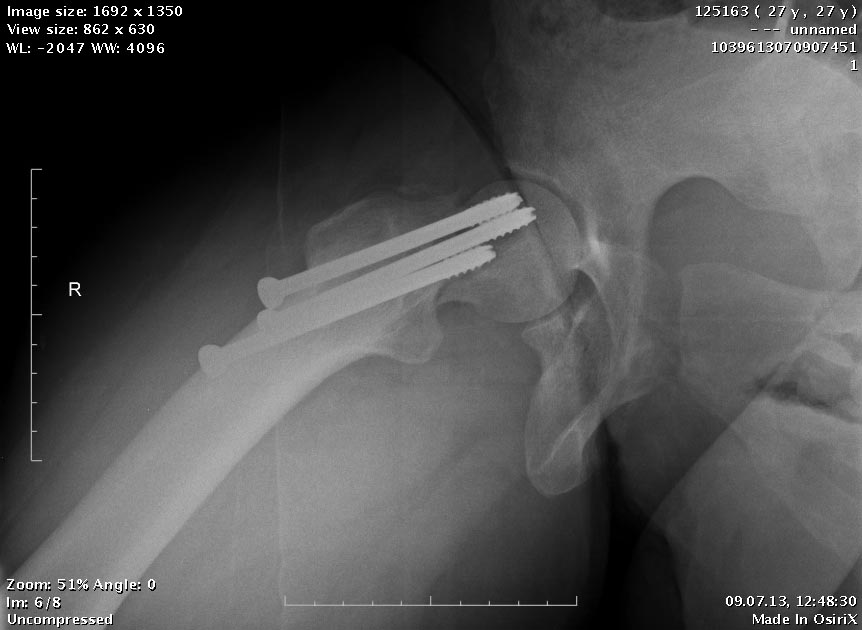

Пациентка приехала на этой неделе. Сегодня сделали правое бедро. Удалили

винты, сделали чрескожную вальгизирующую остеотомию, зафиксировали

Affixus. Второе бедро будем делать недели через 2.